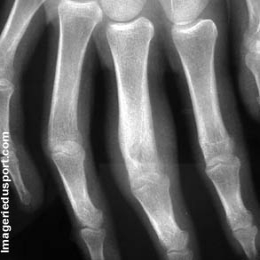

A - Radiographie de face du 3éme doigt : Lacune arrondie excentrée par rapport à l'axe de la phalange, semblant être de départ cortical. Réaction périostée du bord externe de la phalange associée.

B - Radiographie de 3/4 centrée sur le 3éme rayon : Lacune arrondie. La réaction périostée est moins bien visible. Epaississement des parties molles alentours.

Ostéome ostéoïde phalangien.